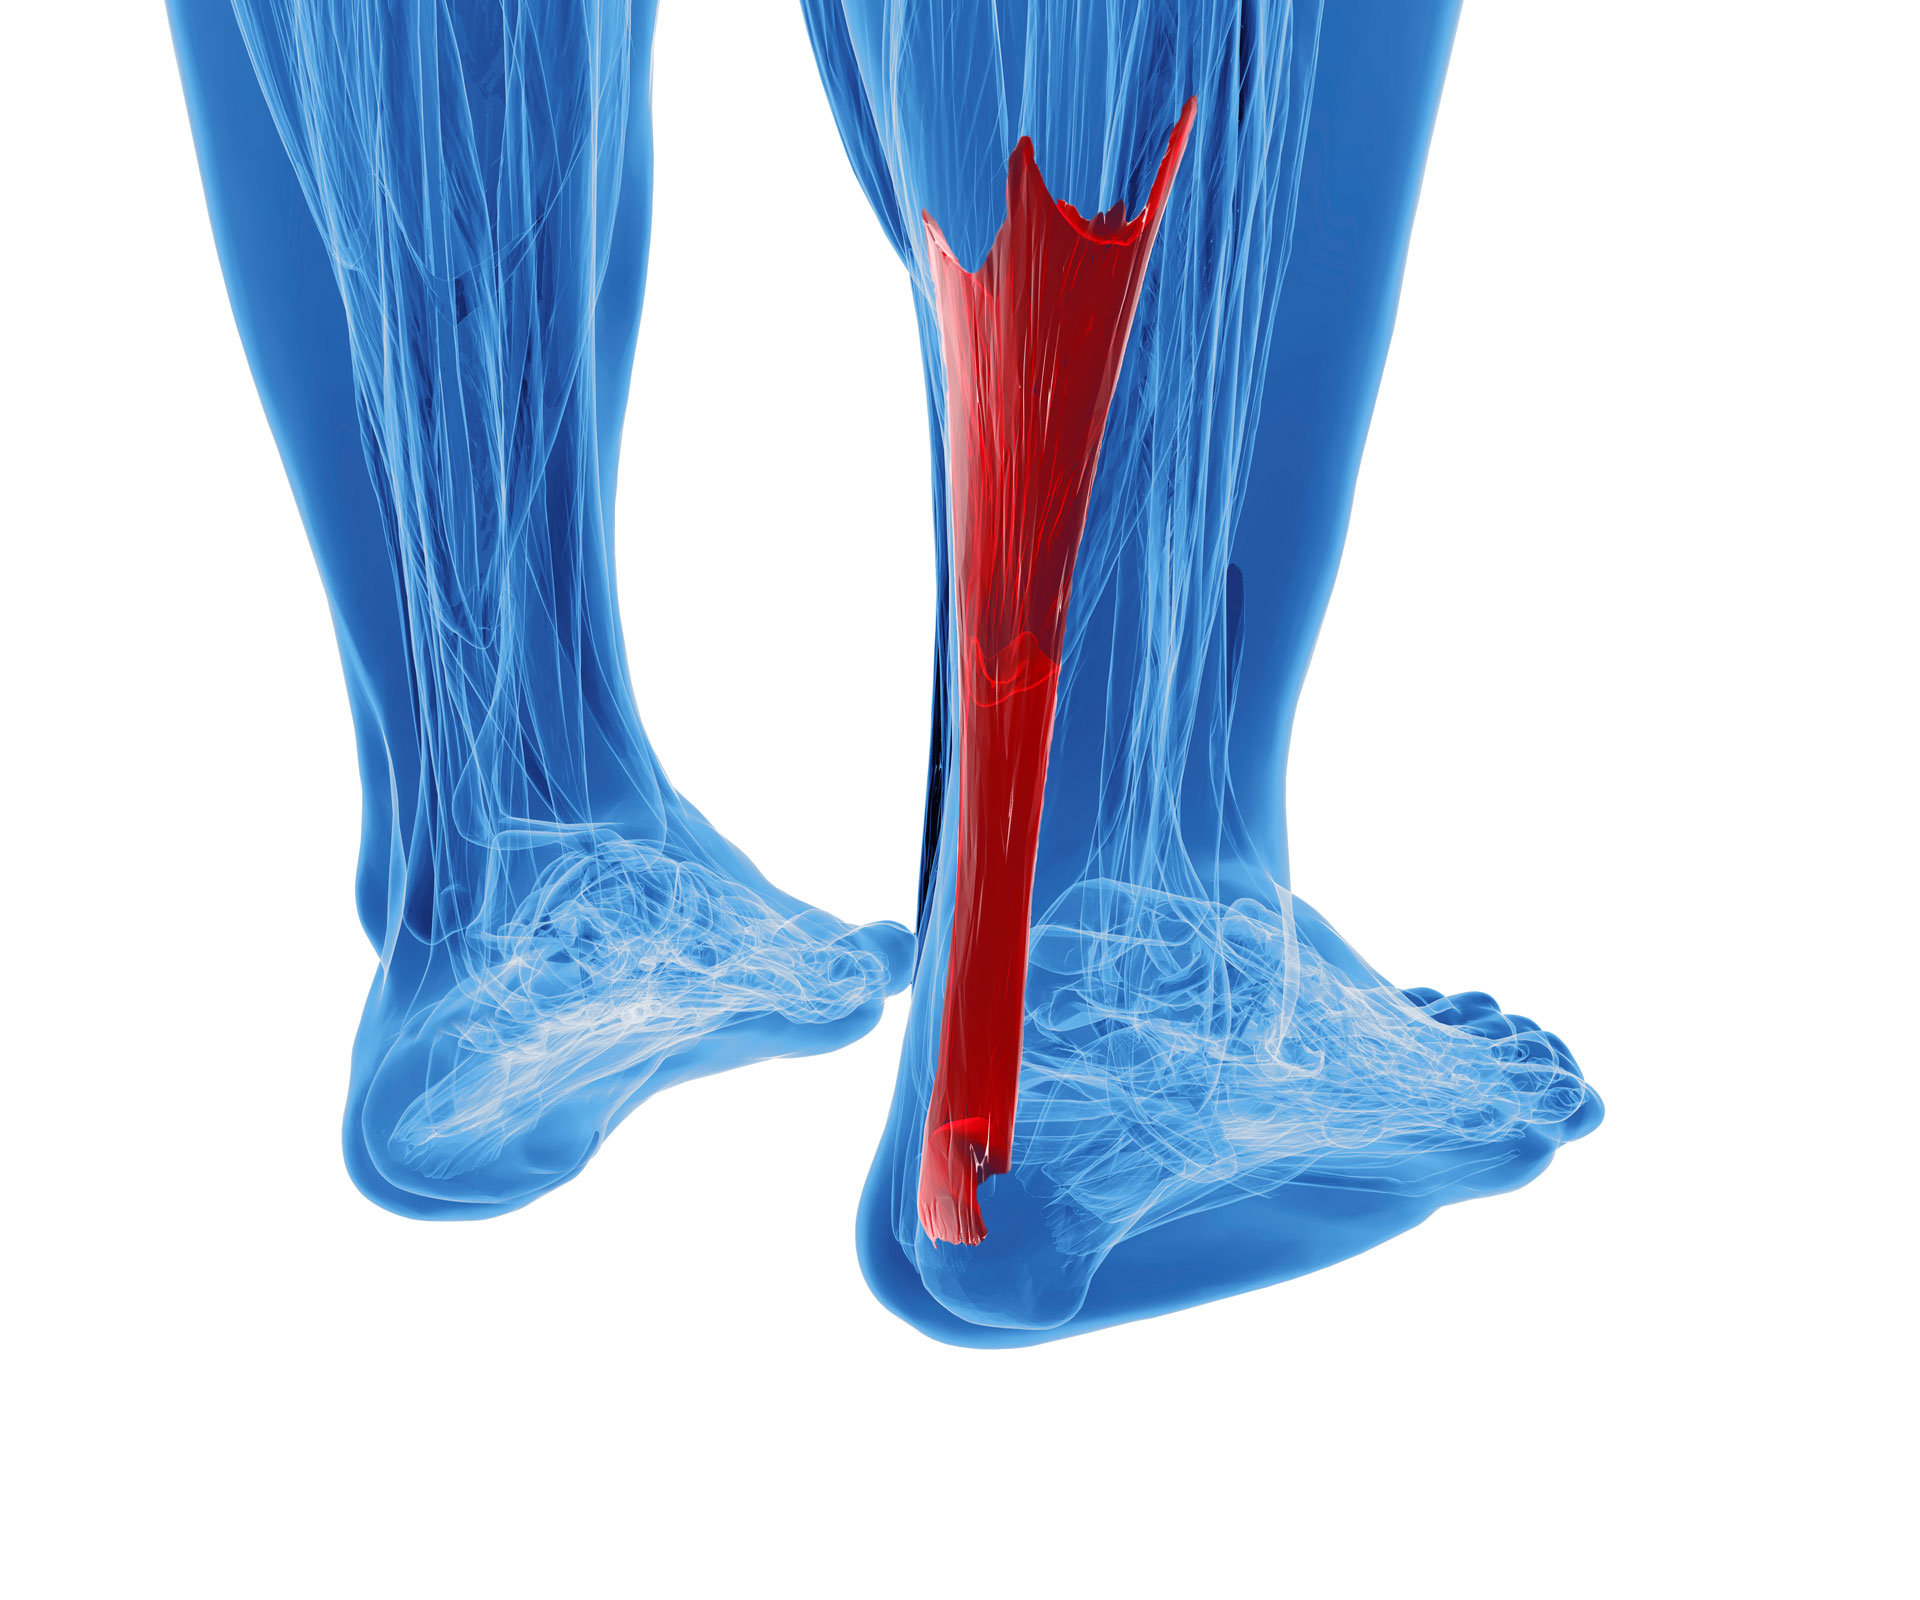

pictures of achilles tendon

Achilles Tendon Rupture stock illustration. Image of tear – 52456557

Musculare hi-res stock photography and images – Alamy

Symptoms of a Torn Achilles Tendon | Healthy Living